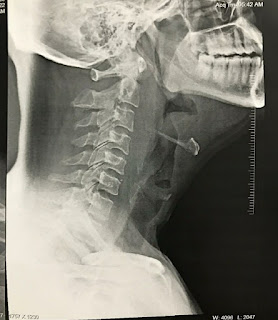

A 36 yr old male patient who is a watchman in a government hospital was admitted at 4AM on 12/01/2022 in the OPD with the chief complaints of

1) Discomfort of the throat since 3-4 hrs

2) Swelling and pain in the throat

PROVISIONAL DIAGNOSIS

Hereditary angioneurotic edema.